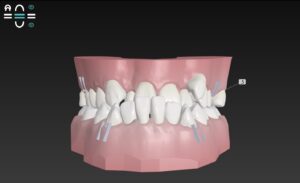

本日は

🔶初診時🔶

正面

受け口で

正式名称 Ⅲ級

あるいはクラス スリー と

歯並びガタガタの そうせい を気にして

マウスピース矯正を希望して来院

今回はインビザラインではなく

インビザラインのジェネリック

クリアコレクトを選択

お口のスキャナー トリオスで

歯並びをスキャン